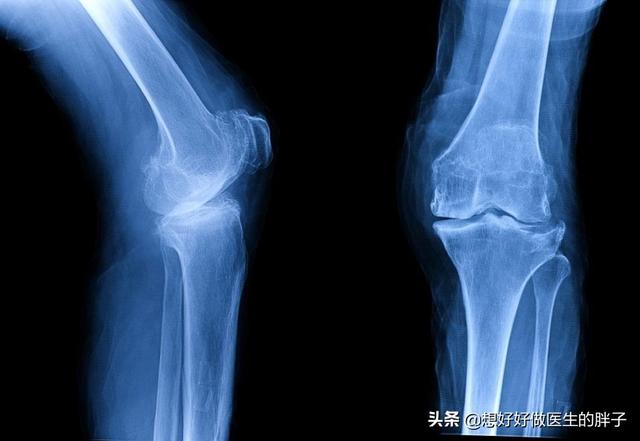

针对于这种情况,最好还是要明确关节腔内软骨磨损的具体情况,建议患者不仅要进行膝关节x线检查,还应该检查膝关节的核磁,如果关节内软骨磨损不是特别的严重,可以给予患者关节内注射玻璃酸钠或者是prp来增加软骨的弹性,尽量润滑关节,帮助患者减轻症状。随着症状的减轻,患者的行动力也会有所增加,如果在进行科学的康复锻炼,强化关节周边的肌肉,那么症状就会有所缓解。

而如果膝关节问题比较严重,关节活动已经出现了明显的受限,关节软骨磨损的特别严重,那么应该进行膝关节置换手术,帮助患者解决疼痛的问题以后再进行更加系统的康复锻炼,尽量帮助患者恢复到日常生活当中去,比如像下图这样的x线,表现患者关节腔内的软骨可能已经磨损消失殆尽了,这种情况如果患者疼痛比较严重,进行关节置换是最好的选择,否则患者膝关节疼痛、酸疼、无力的症状很难改善。